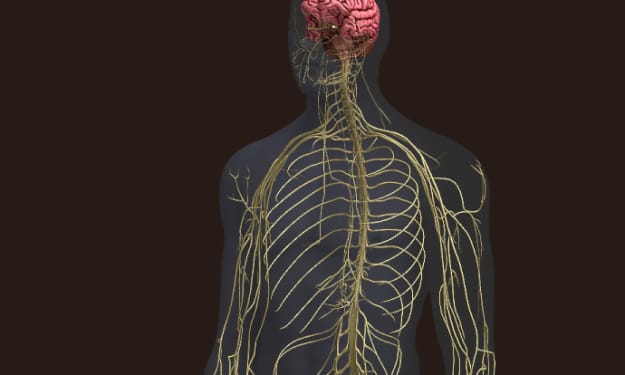

Is our nervous system this complex ???

Title: Unveiling the Power of Synapses: The Incredible Communicators of the Nervous System Introduction: What if I told you that something 1000 times thinner than a piece of paper, more numerous in you than grains of sand on a beach, holds the key to understanding the immense power of the smallest elements in your body? Welcome to the world of synapses, the meeting points between neurons that transform the structure of your nervous system into an extraordinary network of communication and intelligence.

By RAMYA VENUGOPAL3 years ago in Humans

Is our nervous system this complex ???

Title: Unveiling the Intricacies of Neuronal Communication: The Power of Action Potentials Introduction: Imagine a world where every thought, feeling, and action can be communicated by simply pressing a button. It would be like using a simplistic app that emits a constant and uniform ping, conveying everything from "I'm cold" to "I love churros" to "I need to breathe." Interestingly, this concept mirrors how neurons send electrical impulses responsible for all our actions, thoughts, and emotions. Neurons transmit signals through a remarkable phenomenon called action potentials. In this article, we will delve into the fascinating world of neuronal communication, exploring the mechanisms behind action potentials and their significance in our daily lives.

By RAMYA VENUGOPAL3 years ago in Humans

Is our nervous system this complex ???

Title: The Intricacies of the Nervous System: Understanding Its Functions and Organization Introduction Every morning, we go through various routine actions that seem mundane, such as waking up from a dream, getting dressed, having breakfast, and attending to our pets. However, these actions are not merely part of our morning rituals; they are all manifestations of the incredible capabilities of our nervous system. From processing dreams to sensing temperature changes and making decisions, our nervous system controls every aspect of our being. In this article, we delve into the fascinating world of the nervous system, exploring its anatomy, organization, communication, and the consequences of damage.

By RAMYA VENUGOPAL3 years ago in Humans